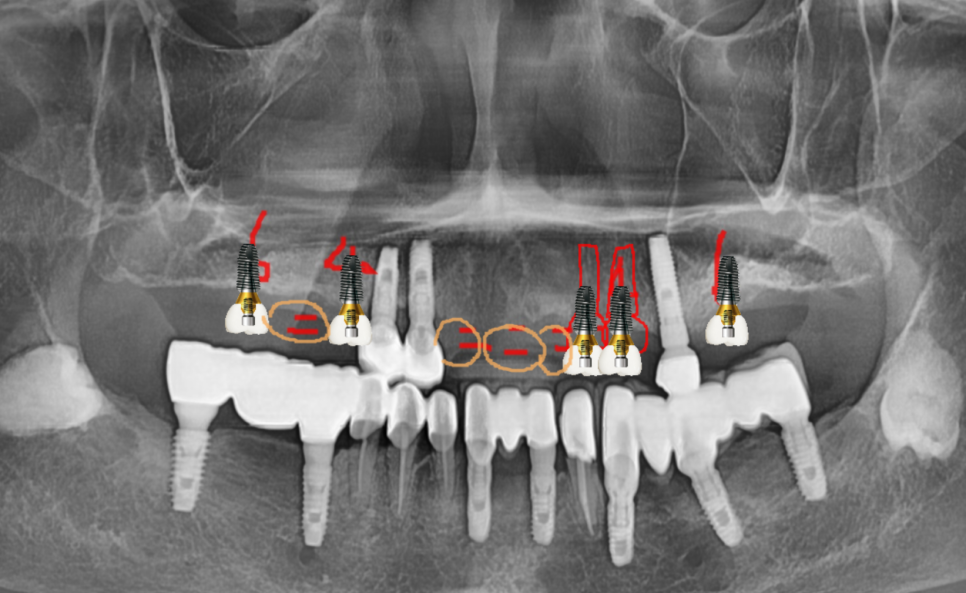

241031 치료계획입니다~~ 기존 심겨진 임플란트를 활용하면서 회복해주는 계획이죠.

치아 높이가 무너진 것 외에

두번째 문제로는 남아있는 치아 개수 차이가 많이 났습니다.

아래 치아는 상대적으로 많고

윗니 치아는 손실이 많았죠.

이렇게되면 틀니로 다시 치료하게 되더라도

궁합이 맞지 않습니다.

힘의 균형이 깨지거든요~

상대적으로 강한 임플란트 치아가

틀니를 자꾸 치니까

틀니에도 문제가 생깁니다.

치아가 깨져나가거나

편하게 식사를 할 수 없는...

수술은 네비게이션 임플란트 방식으로

한번에 진행되었고

치료 과정에서

기존에 심겨진 임플란트는 최대한 활용하였습니다.

높이가 낮아졌다하면

기존 임플란트를 제거해야한다 생각하시는 분들이 있으시더라고요~

임플란트는 뼈 안에 식립되어있고

높이를 올리는 것은 보철을 통해 해결해주기 때문에

문제가 되지 않습니다.